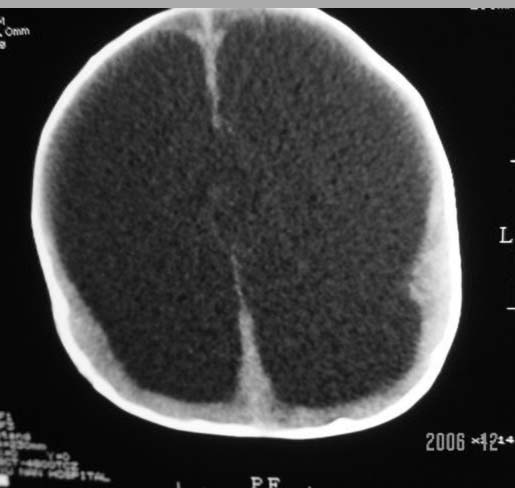

3m,出生时有新生儿吸入性肺炎、hie、化脓性脑膜炎,近一个月发现头围增大(51cm),无恶心呕吐。

3m,出生时有新生儿吸入性肺炎、hie、化脓性脑膜炎,近一个月发现头围增大(51cm),无恶心呕吐,脑室系统全程扩张,脑皮质变薄,结合病史考虑交通性脑积水

3m,出生时有新生儿吸入性肺炎、hie、化脓性脑膜炎,近一个月发现头围增大(51cm),无恶心呕吐,脑室系统全程扩张,脑皮质变薄,结合病史考虑重度交通性脑积水。